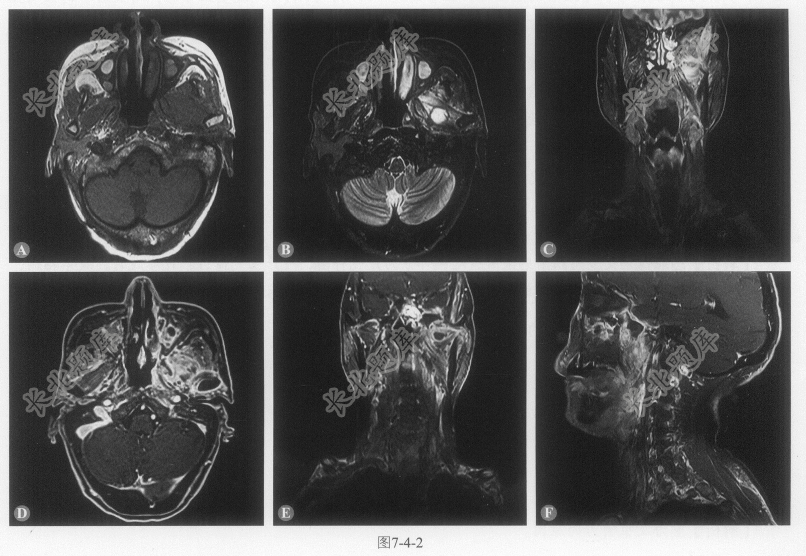

患者男性,61岁,鼻阻伴脓涕40余年,再发加重半月,查体:左侧面颊部肿胀。MRI图像如图7-4-2。

- 多项选择题1.本病例的影像学表现有:

A、左侧咀嚼肌间隙为主见大片状、斑片状等或长T

、长T2信号B、病灶增强后明显不均匀强化,内见不规则囊状无强化区

C、病灶向上累及眼眶、颞部颅板,增强后相应区域脑膜强化

D、病灶累及左侧腭帆张提肌、翼腭窝、翼内外肌、颞肌、咬肌及部分腮腺